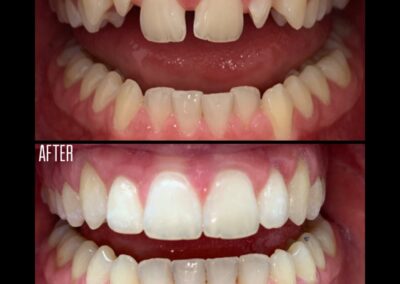

Gallery